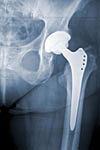

Årligt indsættes der omkring 16.000 hofte- og knæalloplastikker i Danmark. En væsentlig og alvorlig komplikation er dyb infektion, der i langt de fleste tilfælde medfører reoperation og revision af den indsatte alloplastik. Prognosen efter dyb infektion er alvorlig, og den er klart dårligere end efter operation for f.eks. en aseptisk løsning [2].

De danske ortopædkirurger har derfor stor respekt for infektioner og de videnskabelige selskaber har af samme grund i referenceprogrammerne for hofte- og knæalloplastik opstillet klare retningslinjer for forebyggelse af infektion [3]. Som en del af de profylaktiske tiltag anvendes helklæbende plast som en standard til vores operationer.

Der skal ikke herske tvivl om, at DSHK gerne ser, at antallet af infektioner nedsættes, men at de kan øges ved anvendelse af helklæbende plast, er der ingen evidens for i ortopædkirurgien. Samtidig er vi åbne over for ændring af standarder, men det skal ske evidensbaseret. Heldækkende plast anvendes i dag som standard ved stort set alle hofte- og knæalloplastikoperationer og kan ikke umiddelbart fjernes herfra. Det er næppe realistisk set i lyset af den lave infektionsfrekvens at foretage et randomiseret studie, hvor endepunktet er dyb infektion, men vi kan opfordre til, at der udføres studier med surrogat-end points.